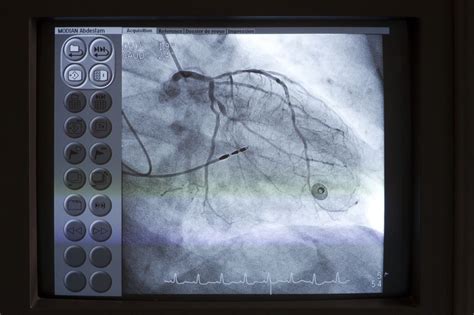

Es un cateterismo, also known as cardiac catheterization, is a medical procedure used to diagnose and treat certain heart conditions. This minimally invasive procedure involves inserting a thin, flexible tube called a catheter into a blood vessel, typically in the groin, arm, or neck, and guiding it to the heart. The catheter is used to measure pressures, take blood samples, and perform various diagnostic tests. In some cases, it can also be used to treat heart conditions by opening blocked arteries or repairing heart valves.

Es un cateterismo is typically performed in a cardiac catheterization laboratory, a specialized room equipped with advanced imaging technology. The procedure involves several steps:

2. Catheter Insertion: A small incision is made in the blood vessel, and the catheter is inserted and guided to the heart using fluoroscopy, a type of X-ray imaging.

3. Diagnostic Tests: Various diagnostic tests are performed, such as measuring pressures in the heart chambers, taking blood samples, and injecting contrast dye to visualize the heart's blood vessels.